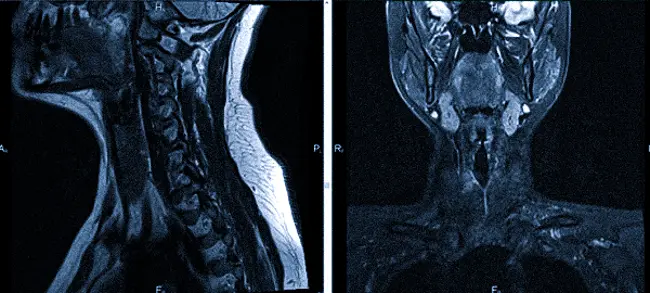

Магнитно-резонансная томография предоставляет возможность детально визуализировать рыхлые структуры. Сканирование генерирует послойные изображения щитовидной железы, лимфатических узлов, кровеносных сосудов и мягких тканей шеи, а также гортани.

Это исследование отличается высокой информативностью по сравнению с другими методами компьютерной диагностики. Томограммы позволяют увидеть изменения в форме и размере анатомической структуры и помогают определить наличие патологий и абнормальных очагов диаметром от 3 мм.

Магнитно-резонансная томография (МРТ) щитовидной железы применяется при наличии подозрений на онкологические, воспалительные, дегенеративные или дистрофические изменения. Этот метод позволяет определить местоположение патологического очага, а также помогает оценить взаимодействие между измененными и здоровыми тканями.

При увеличении объемов железы по данным томограммы возможно установить характеристики гиперплазии. Узловые образования и капсулы проявляются на МРТ как участки с низкой или высокой интенсивностью сигнала, который отличается от реакции ближлежащих тканей. Данное исследование позволяет выявить сдавление трахеи образованием, а также распространение аномальных процессов в загрудинное пространство.